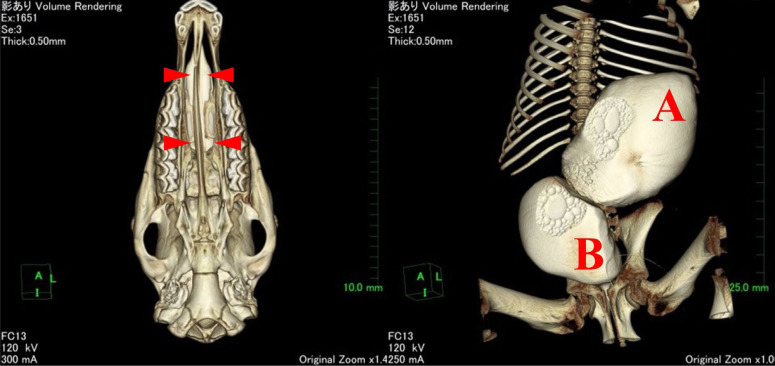

A male foal developing within a pregnant native Hokkaido mare presented with an abnormal bladder on gestational day 215 and was delivered by inducing parturition. Transabdominal ultrasonography indicated a bladder depth of >13 cm, with a wall-like structure bisecting the bladder. At 42 hr after birth, transnasal endoscopy revealed a cleft hard palate, and the foal was subsequently euthanized. A defect in the palatine process of the maxillary head and a large cyst connected to the bladder, although not continuous with the umbilicus, were identified by autopsy computed tomography and necropsy. The foal was accordingly diagnosed with a cleft median hard palate and urachal dysplasia.